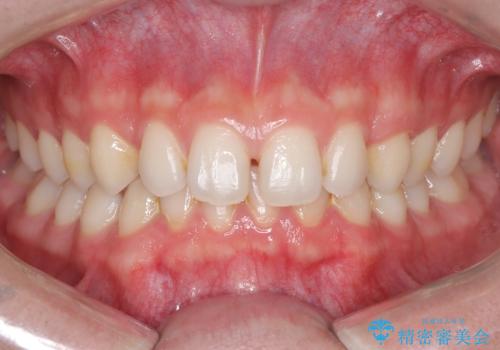

- 主訴:上の歯列の空隙を閉じたい

上顎前歯部に空隙が目立ちました。ワイヤー矯正、インビザライン(マウスピース矯正)どちらの方法でも適用症例と説明し、ワイヤー矯正治療(審美装置)を希望されました。

上顎歯列の空隙を閉じるのと一緒に、ディープバイト気味の被蓋も下顎前歯の圧下を行い改善しました。